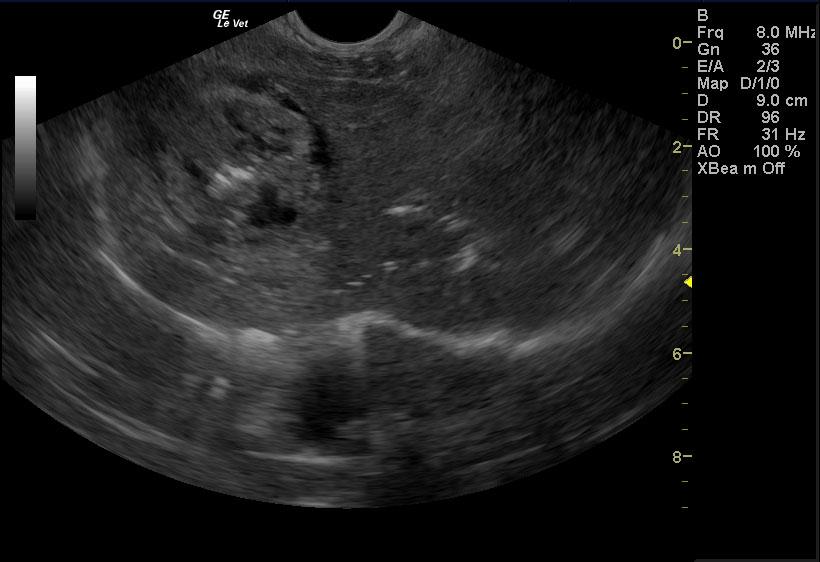

A 15 year old female spayed mixed canine with a history of decreased appetite, diarrhea, and ataxia was presented for evaluation of being unable to walk, weak and lethargic, anorexic, and possible seizures. Abnormalities on serum biochemistry were severely elevated liver enzyme activity, bilirubinemia, hypokalemia, and elevated pre-prandial bile acids. Systolic blood pressure was normal.